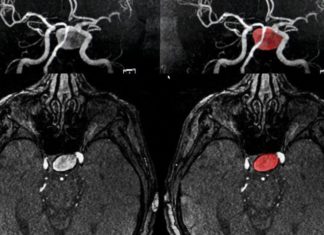

Una nueva herramienta de detección identifica a las personas en riesgo...

Se llama asesino silencioso. Las advertencias son raras, pero del millón de personas que sufren la rotura de un aneurisma cerebral cada año, casi...